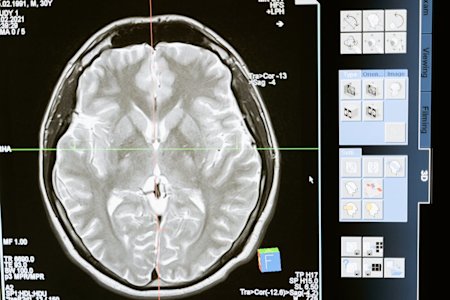

Natuurlijk kunnen radiologen geen MRI-machines inpakken en meenemen naar huis. Echter, remote access-technologie kan radiologen helpen om toegang te krijgen tot hun werkapparatuur om scans te bekijken, gezondheidsdossiers veilig te openen en te overleggen met andere experts, ongeacht waar ze zijn.

Picture Archiving and Communication System (PACS) dat medische beelden opslaat, beheert en distribueert van overal, met gebruik van het Digital Imaging and Communications in Medicine (DICOM) formaat om zeker te stellen dat ze zichtbaar en toegankelijk zijn op verschillende apparaten.

Cloud-gebaseerde rapportage en beeldvorming technologie om radiologen veilig toegang te geven tot scans en samen te werken met artsen en specialisten op afstand.